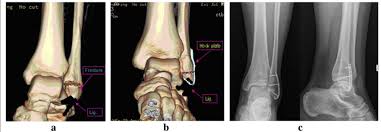

Three Dimensional Computed Tomography Mapping Of Posterior Malleolar Fractures

Three Dimensional Computed Tomography Mapping Of Posterior Malleolar Fractures from f6publishing.blob.core.windows.net